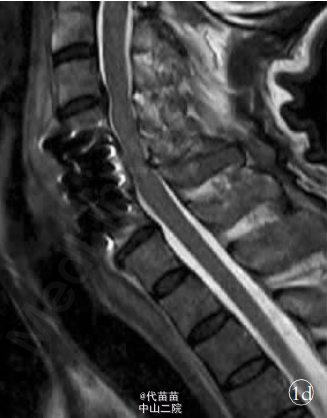

患者,男,61岁。 因高处坠落致颈部疼痛 2h余入院。 查体:C4-C6棘突压痛明显,活动受限,稍有肿胀,双上肢感觉麻木伴有痛觉过敏,双侧肱二头肌肌力Ⅳ级,双手握力下降,双下肢感觉活动可,肢端感觉血供可。入院时实验室检查均未见明显异常。 MRI 检查显示 C3-C7 椎间盘后突伴 C4-C6 平面椎管狭窄,颈髓受压,髓内见小片高信号影,颈椎退行性改变(图1a)。 诊断:①颈椎病;②颈髓损伤。 手术:采用全身麻醉,取颈部右侧斜行切口,长约 6 cm,逐层切开皮肤、颈阔肌,沿气管食管与胸锁乳突肌、颈动静脉鞘间隙分离暴露椎前筋膜,分离椎体前筋膜,摄定位X线片,将前纵韧带切开,显露病变椎体及椎间盘, 先用角度刮匙和髓核钳切除病变段椎间盘及上下 终板,用高速磨钻行病变椎体大部分切除,显露硬脊膜和致压物。 小心分离致压物,彻底解除脊髓压迫。 植入大小适中填满松质骨的钛网, 再将长短合适的颈前路钢板系统通过螺丝钉固定于开槽减压区上下方椎体上。 C 形臂 X 线机透视证实钢板系统位置正确后,切口内置负压引流管,逐层缝合切口。 手术顺利,出血约 200 ml。 术后 48 h 切口引流量约 50 ml,拔除引流管。术后复查 X 线片示内固定位置可(图 1b,1c)。术后查体:双上肢感觉无麻木,双侧肱二头肌肌力Ⅳ级强,双手握力Ⅳ级,双下肢各肌群肌力Ⅴ级,感觉活动可。 术后第 5 天突发神志不清 ,躁动不安 ,查体 :双上肢肌 力Ⅲ级 ,双 下 肢 肌 力0 级,病理反射未引出。 急查头颅 CT、血电解质、血气分析等 均未发现明显异常, 胸部 CT 示双肺下叶炎症伴两侧胸膜反应。 经相关临床科室会诊后转入 ICU 监护,予抗感染,加强龙冲击等对症支持治疗。复查头颅 MRI、DWI、MRA,胸腰椎 MRI均未见明显异常, 颈椎 MRI 示:C4-C6 椎体内固定术后改变,颈髓受压,髓内见小片高信号影(图 1d)。 经外院脊柱外科专家会诊: 颈髓受压影像考虑为内固定产生伪影所致。 术后第10 天,患者情况较前明显好转,转入我科继续抗感染、营养神经、针灸等对症治疗。 查体:神志清,切口愈合良好,平乳头平面以下感觉麻木,双侧肱二头肌肌力Ⅲ级,双下肢股四头肌肌力Ⅰ级,双侧胫前肌、拇长伸肌肌力 0 级,巴彬斯基征阳性,奥本汉姆征阳性。 术后 15 d 双下肢股四头肌、胫前肌肌力较前出现好转。 术后 20 d 双下肢肌群肌力恢复至Ⅲ级水平。 术后45d双上肢肌群肌力Ⅴ级,双下肢肌群肌力Ⅵ级强,已下地步行训练。 近年来, 颈椎前路减压植骨钢板螺钉内固定术已普遍运用于颈椎疾病的治疗中,然而手术后并发症也时有发生。本例患者术后近 1 周突发下肢截瘫,1 个月后又基本恢复,实属罕见。 分析原因:①考虑术后血肿形成,压迫脊髓造成相应症状出现。②考虑内植物松动移位。 ③可能与术后感染,脓肿压迫神经组织有关。 然而标准的颈前路手术有 1%~3% 的创口感染率。本例患者术后切口愈合良好,无红肿及液性渗出,颈椎 MRI 检查未见明显脓肿形成。 虽有肺部感染情况发生,但不足以构成对神经系统的损伤,导致截瘫的发生。 仔细回顾病史,患者曾有长年酗酒史,术后出现过意识 模糊,并伴有全身抽搐现象,复查电解质示血钙、血钠有异常,这与截瘫的发生不无关系。 有研究表明,对于长期酗酒患者,酒精戒断容易出现神经及精神方面症状。 而戒断性癫痫发作好发于长期饮酒后造成慢性酒精中毒的男性, 包括老年人在内的各年龄段都有可能发生,可无潜在的异常放电病灶,即头颅 MRI 或 CT检查未见明显异常。本例患者头颅相关检查并无异常,但电解质出现紊乱,且伴有高热、肺炎症状,加之以往有酗酒史,戒断综合征是不得不考虑的原因之一。 患者尽管已行前路钢板内固定,但颈椎的承受力远远未达到生理功能的要求,强烈的全身抽搐极有可能造成对颈髓的损伤,造成难以预计的后果。但神奇的是在截瘫后 1 月余,患者又逐渐恢复正常。查阅相关文献,尚未见有相关类似的报道。 对于此类患者,术前需仔细询问既往史,特别是酗酒史,防止戒断综合征的产生,术后加强监护,加强营养神经等对症支持治疗。